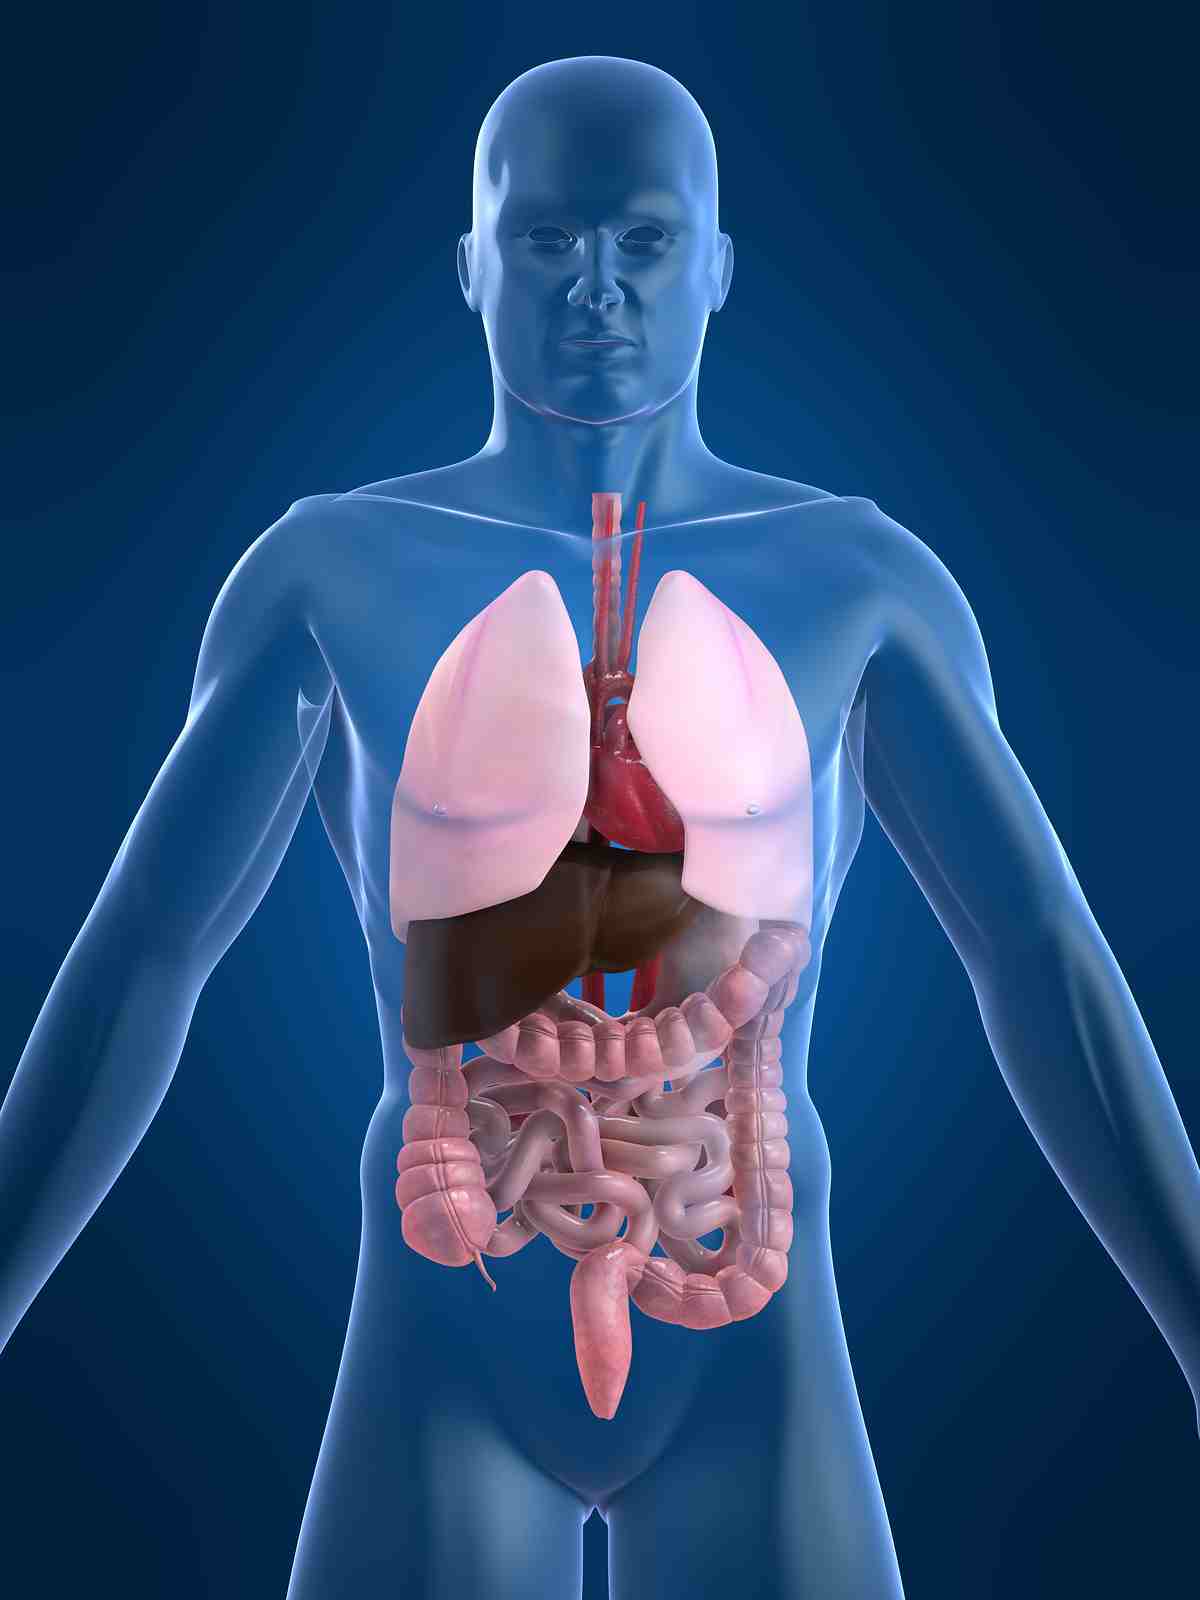

Анатомия желудка и сердца: визуализация и изучение

Раздел: Фотопанорама